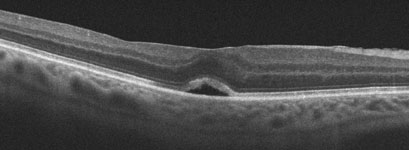

You can’t diagnose a macular hole by looking in the mirror since your eye will usually look and feel normal. The diagnosis is made with a thorough retinal examination through a dilated pupil. Early stages of macular hole formation are often difficult to diagnose, often requiring additional testing such as OCT scanning which offers a near microscopic macular image.

Vitrectomy surgery is performed in the operating room under local anesthesia. This advanced microsurgical technique allows us to restore vision by peeling and removing the vitreous from the macular surface and then filling the eye with a special gas bubble. The gas bubble helps to seal and flatten the hole postoperatively.

Patients go home immediately following surgery. There is usually minimal to no pain, except for minor irritation from sutures which absorb within several weeks of surgery. Patients need to look down to the floor for 1 week, which properly positions the gas bubble against the macular hole. Special equipment is available to help patients comfortably maintain this positioning (Comfort Solutions, Kelly Comfort Solutions, Vitrectomy Solutions) or watch TV while looking down (Make It Rite Mirror). Airplane flying and driving to higher altitudes is strictly prohibited while the bubble is present since it can expand causing severe pain and possible blindness. Even if the eye will ultimately see well, vision will be quite poor for a few months since the eye is not designed to see well through the bubble. The gas bubble absorbs on its own over several weeks to months, at which point it is possible to tell whether or not the hole has flattened. Vitrectomy successfully flattens the macular hole in over 90% of cases. With successful surgery, vision usually improves by about 50% although it may take several years for maximal vision to return.